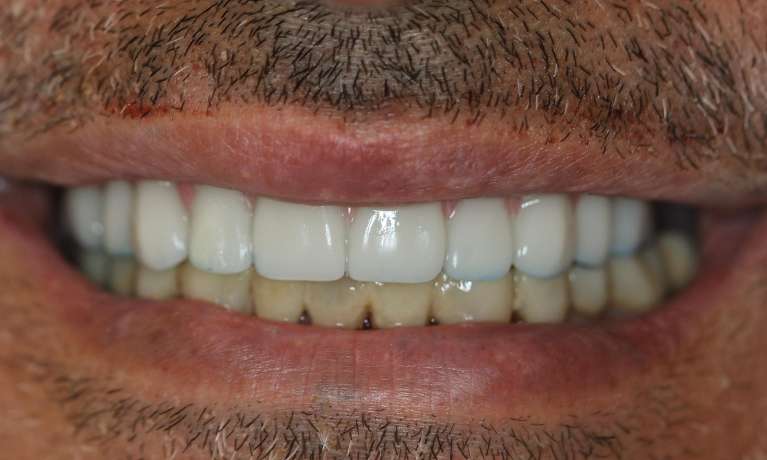

This patient arrived with several missing and decayed teeth, impacting both their oral health and confidence. Through the innovative All-on-4 dental implant procedure, they received a complete, beautiful and functional new smile.